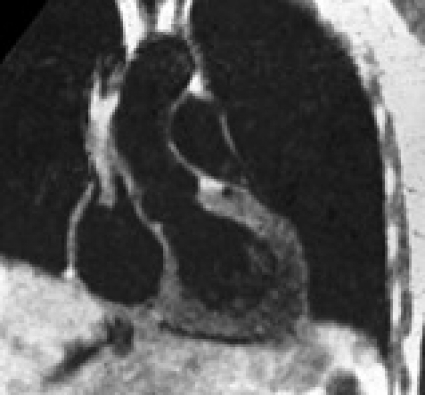

Tekniken blev medicinskt användbar

Utvecklingen av en medicinskt användbar avbildande NMR-teknik skedde härefter, och det finns ett antal forskare som bidragit till den snabba utvecklingen av tekniken, främst Paul Lauterbur och sir Peter Mansfield, som erhöll Nobelpriset i fysiologi eller medicin år 2003 [10] för deras arbeten med att positionsbestämma NMR-signalen med hjälp av fältgradienter, nya pulssekvenser, metoder för databearbetning etc (Figur 5).